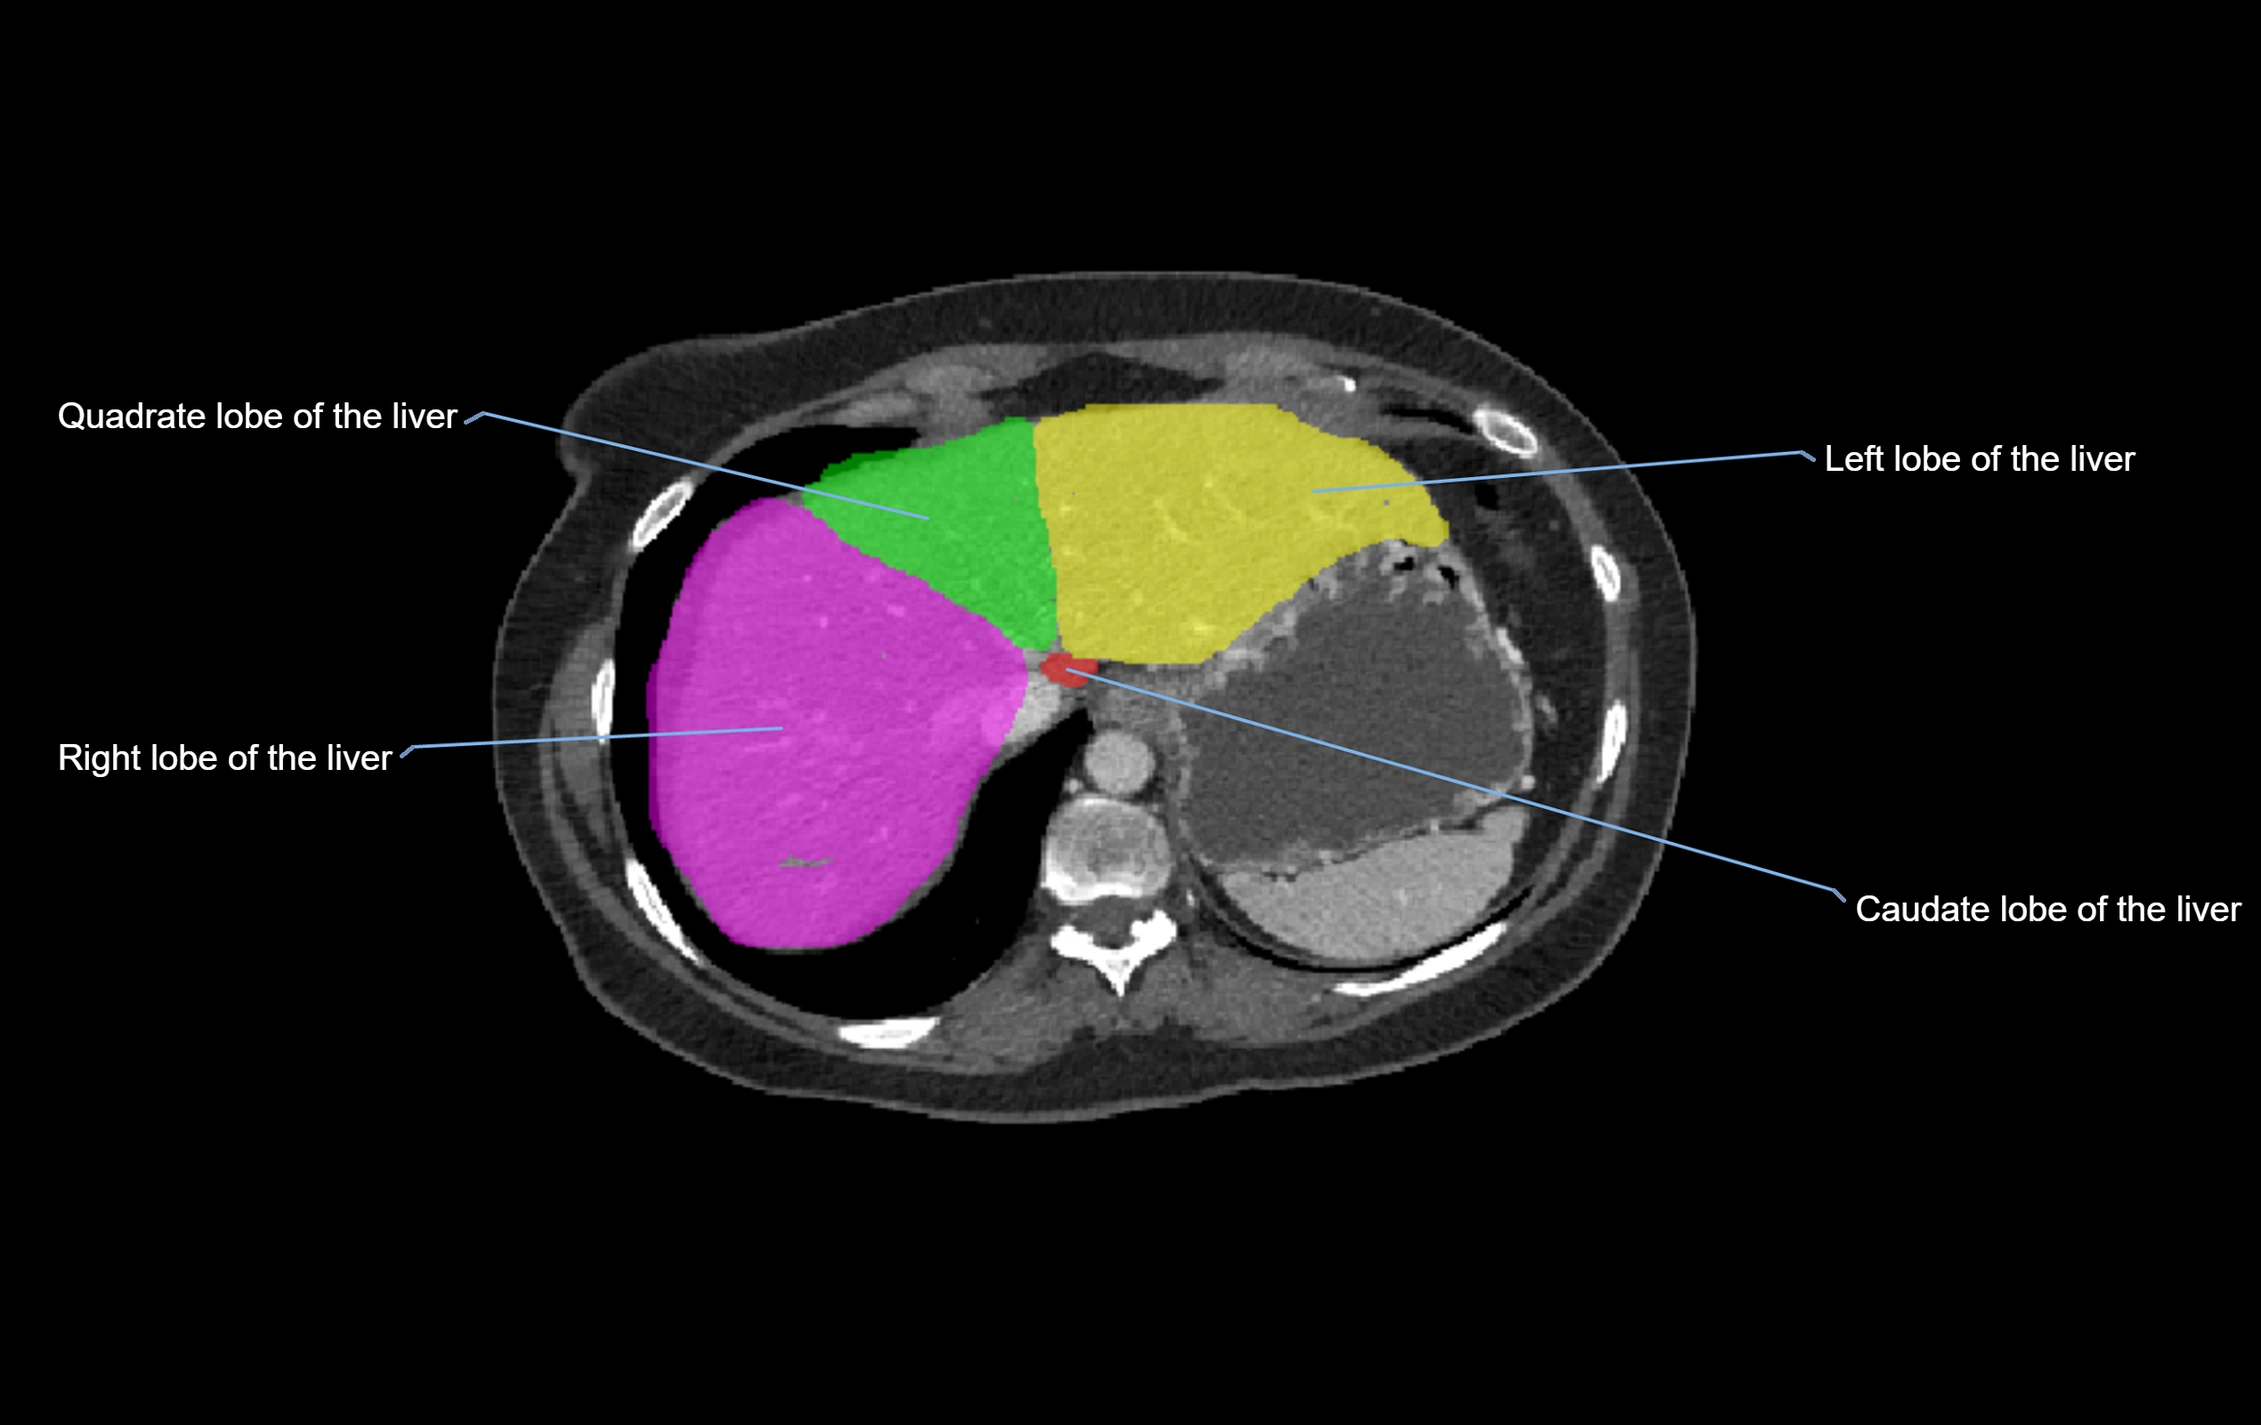

CT Image

image